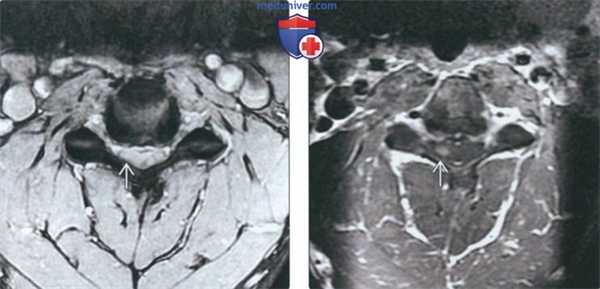

(Слева) На аксиальном T2*GRE МР-И видны признаки умеренно выраженного фораминального стеноза на фоне относительно легких дегенеративных изменений дугоотростчатых суставов и гипертрофии унковертебральных суставов. Спинной мозг с признаками усиления сигнала вследствие хронического сдавления и миеломаляции.

(Справа) Т1-ВИ с КУ: признаки фораминального стеноза вследствие гипертрофии унковертебральных суставов и дегенеративных изменений дугоотростчатых суставов, в толще спинного мозга виден очаг усиления сигнала, представляющий собой зону миеломаляции.

(Слева) На аксиальной МРТ (T2*GRE) определяется умеренный фораминальный стеноз, обусловленный легкими детенеративными изменениями дугоотростчатых суставов и гипертрофией унковертебральных суставов. Гиперинтенсивный сигнал в спинном мозге обусловлен его хроническим сдавлением и миеломаляцией.

(Справа) На аксиальной MPT (Т1ВИ C+) определяется фораминальный стеноз на фоне гипертрофии унковертебральных суставов, дегенеративных изменений дугоотростчатых суставов и миеломаляции с накоплением контраста в спинном мозге.